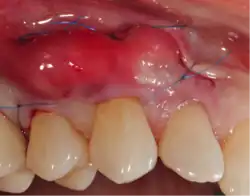

A small amount of blood (10 millilitres (0.35 imp fl oz; 0.34 US fl oz) per tube) is harvested and spun in a centrifuge for eight minutes at 1300 RPM. A fibrin clot packed with blood-derived growth factors, extra cellular matrix and hematopoietic stem cells is fabricated and implanted into the gums above the area of gum recession. Advanced platelet-rich fibrin will promote the patient's own gums to fabricate more gum thus eliminating the need to harvest gums from the roof of the mouth or the use of allografting tissue.

Traditional gum grafting will have a piece of the gums harvested from the roof of the mouth and sutured facing the exposed root to increase the lost keratinized tissue.[11] The limitation in quantity and the morbidity are the limiting factor of this technique. Allografting techniques (skin from cadavers bought from tissue banks) are used as well to supply the surgeon with larger amount of tissues when needed in larger cases,[12] but the type of healing and the risk of possible disease transmission should be considered and disclosed to the patient when opting for such technique.[13]

Advantages of APRF in gum grafting

Blood-derived growth factors have been used in medicine and oral surgery for more than twenty years with an abundance of scientific data supporting its role in soft and hard tissue regenerations. APRF introduced by Dr. Choukroun represents the fourth improved generation of such technology and has been widely used in the field of dentistry and oral surgery. The advantages of APRF are of multiple folds: Unlimited amount (only 10 millilitres (0.35 imp fl oz; 0.34 US fl oz) per tube harvested), no risk of rejection or disease transmission (using your own blood), high noble type of healing (autogenous growth factors, hematopoietic or mesenchymal stem cells).[14]